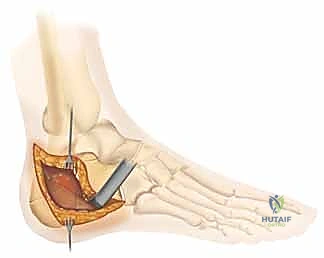

2. تقنية "عدم اللمس" (No-Touch Technique)

للحفاظ على حيوية الأنسجة الرقيقة (السديلة الجلدية)، يستخدم الدكتور هطيف أسلاك كيرشنر (K-wires) لرفع الجلد بعيداً عن مجال الرؤية دون استخدام مبعدات قاسية قد تدمر الأنسجة. هذه التقنية المتقدمة هي سر التئام الجروح السريع بدون نخر (Necrosis).

3. كشف الكسر وإعادة البناء (Reduction)

بمجرد كشف العظم، يتم تنظيف التجمع الدموي. يقوم الجراح بكشف السطح المفصلي المكسور. باستخدام أدوات دقيقة، يتم رفع الشظايا العظمية المنخسفة إلى مكانها التشريحي الأصلي. يتم استعادة ارتفاع وعرض العظم، والأهم من ذلك، استعادة السلاسة التامة لسطح المفصل.

4. التثبيت المؤقت

يتم استخدام أسلاك معدنية دقيقة لتثبيت الشظايا في مكانها مؤقتاً، ثم يتم التحقق من دقة الرد باستخدام جهاز الأشعة السينية داخل غرفة العمليات (C-arm) لضمان عدم وجود أي انزياح ولو بمليمتر واحد.